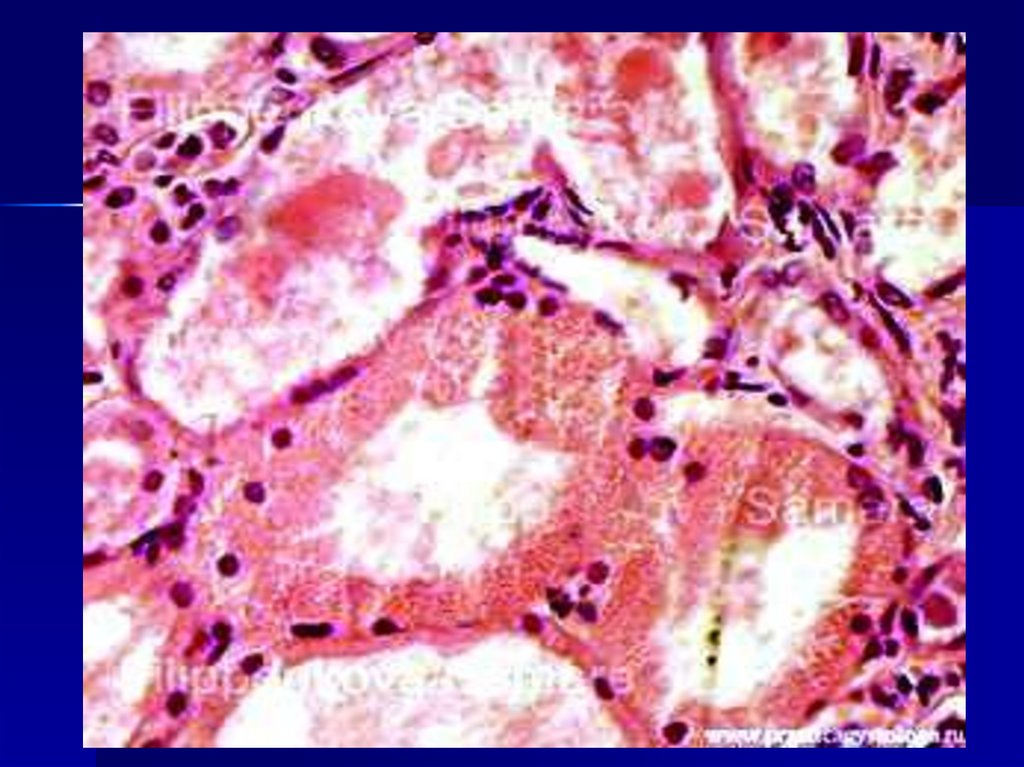

Гиалиново-капельная

В цитоплазме появляются

крупные гиалиноподобные

белковые капли (в результате

коагуляции белка),

сливающиеся между собой и

заполняющие тело клетки,

которые разрушают структуры

клеток.

Гиалиново-капельная дистрофия

эпителия канальцев почки.

ИСХОД:

завершается необратимым

процессом ведущий к

коагуляционному (сухому)

некрозу.

(содержит много белка и мало

жидкости).

Встречается в почках, редко в

печени.

Внешний вид органа

определяется особенностями

заболевания.